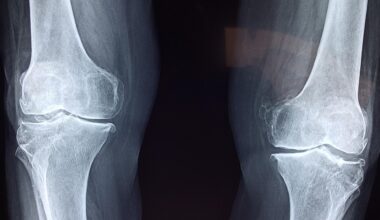

Corticosteroids have become a focal point in the realm of sports medicine, often sparking debates among healthcare professionals, athletes, and sports organizations. These powerful anti-inflammatory agents are utilized to manage various conditions, including tendonitis, bursitis, and certain allergies. While their benefits can be significant, the use of corticosteroids in sports brings forth a series of ethical and health-related concerns. Many athletes seek these medications to accelerate recovery from injuries, which raises questions about fairness in competition and the potential for misuse. Moreover, the effects of long-term use remain a topic of ongoing research, with risks including complications like osteoporosis and cardiovascular issues. Understanding both the therapeutic advantages and the complications associated with corticosteroids is vital for athletes and coaches. The potential for performance enhancement and recovery is tempting; however, these advantages can lead to a breach of ethical considerations in competitive sports. It is essential for athletes to weigh the pros and cons when considering corticosteroid treatment. Education and comprehensive consultations with healthcare providers can play a crucial role in this decision-making process.